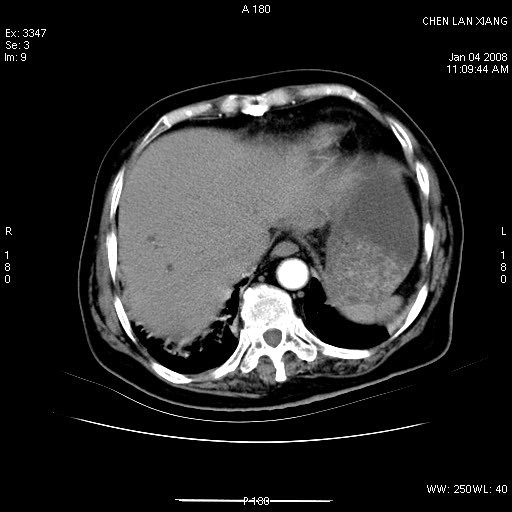

标题: CT11180:女,76岁,腹痛3-4天 [打印本页]

女,76岁,腹痛3-4天,b超示:肝内实性肿物,胆囊强回声,胆总管扩张.

考虑:1、胆总管下端结石伴梗阻性肝内外胆管扩张(肝左叶外侧段肝内胆管多发结石、胆管炎);

2、肿囊癌累及肝,不除外 黄色肉芽肿性胆囊炎。

1 胆总管末端结石伴肝内胆管结石,肝内外胆管扩张。2 胆囊扩大,胆囊壁不规则增厚,内见软组织密度影。考虑:慢性胆囊炎,不除外胆囊癌!

标题: 肝右叶病灶

胆囊癌侵犯肝右叶?

1)胆囊癌伴肝脏转移。2)胆总管下端结石、肝内胆管结石伴肝内外胆管扩张。